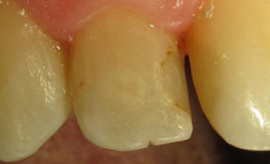

KONZERVATIVA - KOMPOZITNE ZALIVKE ![]()

Kompozitna zalivka nadomešča izgubljeno zobno strukturo (zaradi kariesa ali loma), v primerih, ko okvara na zobu ni prevelika. V preteklosti so se uporabljali neestetski materiali, kot je amalgam. Danes se amalgam skoraj ne uporablja več zaradi slabe vezi z zobom in »kovinskega« nenaravnega videza. Kompozitni materiali, ki jih uporabljamo danes, so estetski, imajo odlične mehanske lastnosti in se dobro vežejo na strukturo zob (če se uporablja pravilno).

Za zdravljenje majhnih, površinskih kariesov, popravilo majhnih defektov in nepravilnosti ter popravilo manjših estetskih nepravilnosti v obliki in barvi zob uporabljamo najmanj invazivne metode odstranjevanja kariesa s posebnimi svedri za minimalno invazivno preparacijo, ki izbrusi le karies ali odstrani staro plombo, zdrava zobovina pa ostane nedotaknjena. Takšni posegi so praviloma neboleči tudi brez anestezije. Kadar pa gre za obsežnejši karies, zlom zoba ali menjavo večje plombe nujna je obsežnejša preparacija ter bolj zapletene tehnike izdelave plomb. Pri tem uporabljamo najnovejše nadstandardne plombirne materiale, saj imajo vrsto prednosti pred klasičnimi zalivkami. So izredno obstojni, estetski ter prijazni zdravju in okolju.

Kompozitne zalivke se izdelujejo tako, da zvesto posnemajo videz naravnih zob. To pomeni, da se s pomočjo kompozitnega materiala oblikuje vsaka jamica in vršek, ki jih ima naravni zob, prehod med zobmi in zalivko pa mora biti neopazen. Na modeliranju jamiv in vrškov ne vztrajamo samo zaradi estetike, temveč tudi zaradi funkcionalnih razlogov. Vsaka zalivka ali krona z razlogom natančno posnema videz naravnih zob. Če tega ne bi upoštevali, bi prišlo do motnje pri naravni razporeditvi sil pri vgrizu, kar lahko povzroči resne zaplete v ustni votlini (izraščanje nasprotnega zoba, če je zalivka prenizka, zatikanje hrane med zobmi in krvavitev dlesni, slab zadah in nastanek žepov).

Če poseg opravljamo na mrtvem zobu (zobu, ki ima zdravljene ali odmrle koreninske kanale), so posegi neboleči. Pri živih zobeh pa se individualno odločamo o anesteziji glede na občutljivost pri vrtanju oziroma pacient sam pove ali želi anestezijo. V primeru, da uporaba kompozitnih materialov ni mogoča, se odločimo za izdelavo keramičnih zalivk (inlay, onlay) ali naredimo prevleko. Inlay in onlay so v zobotehničnem laboratoriju izdelane keramične zalivke, ki se cementirajo na zob. Z njimi dosežemo visoko estetiko, boljšo obstojnost in trdnost od klasičnih zalivk. Lahko služijo kot nosilci členov manjkajočih zob in so tako alternativa klasičnim mostičkom.

V naši ordinaciji amalgamskih zalivk ne izdelujemo. Pri njihovem odstranjevanju pa uporabljamo najvarnejše metode.